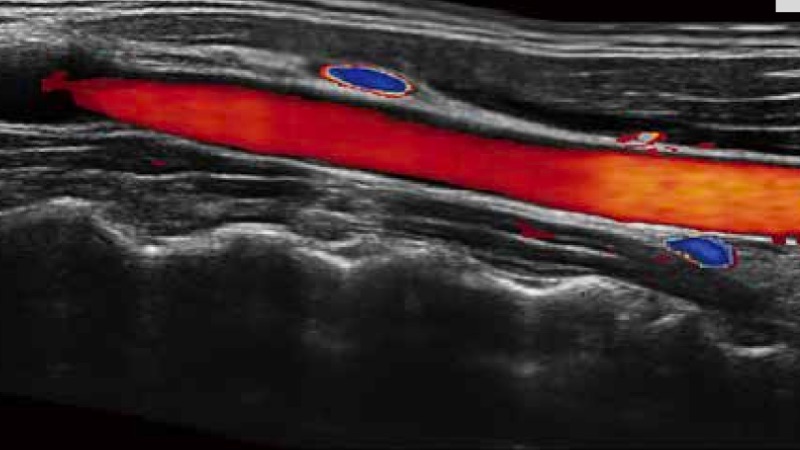

SR Flow高分辨率血流成像

高分辨率血流成像技术提高了对低速血流信号的检测能力。在提高空间分辨率的同时,也克服了血流外溢现象,为用户提供更加真实的血流动力学信息。

通过彩色血流和实时宽景相结合,可观察到完整的动静脉血流,方便医生检查。实时扫查过程中,如有任何操作失误也可以很容易地进行回扫擦除,而不会中断扫查。

临床图像